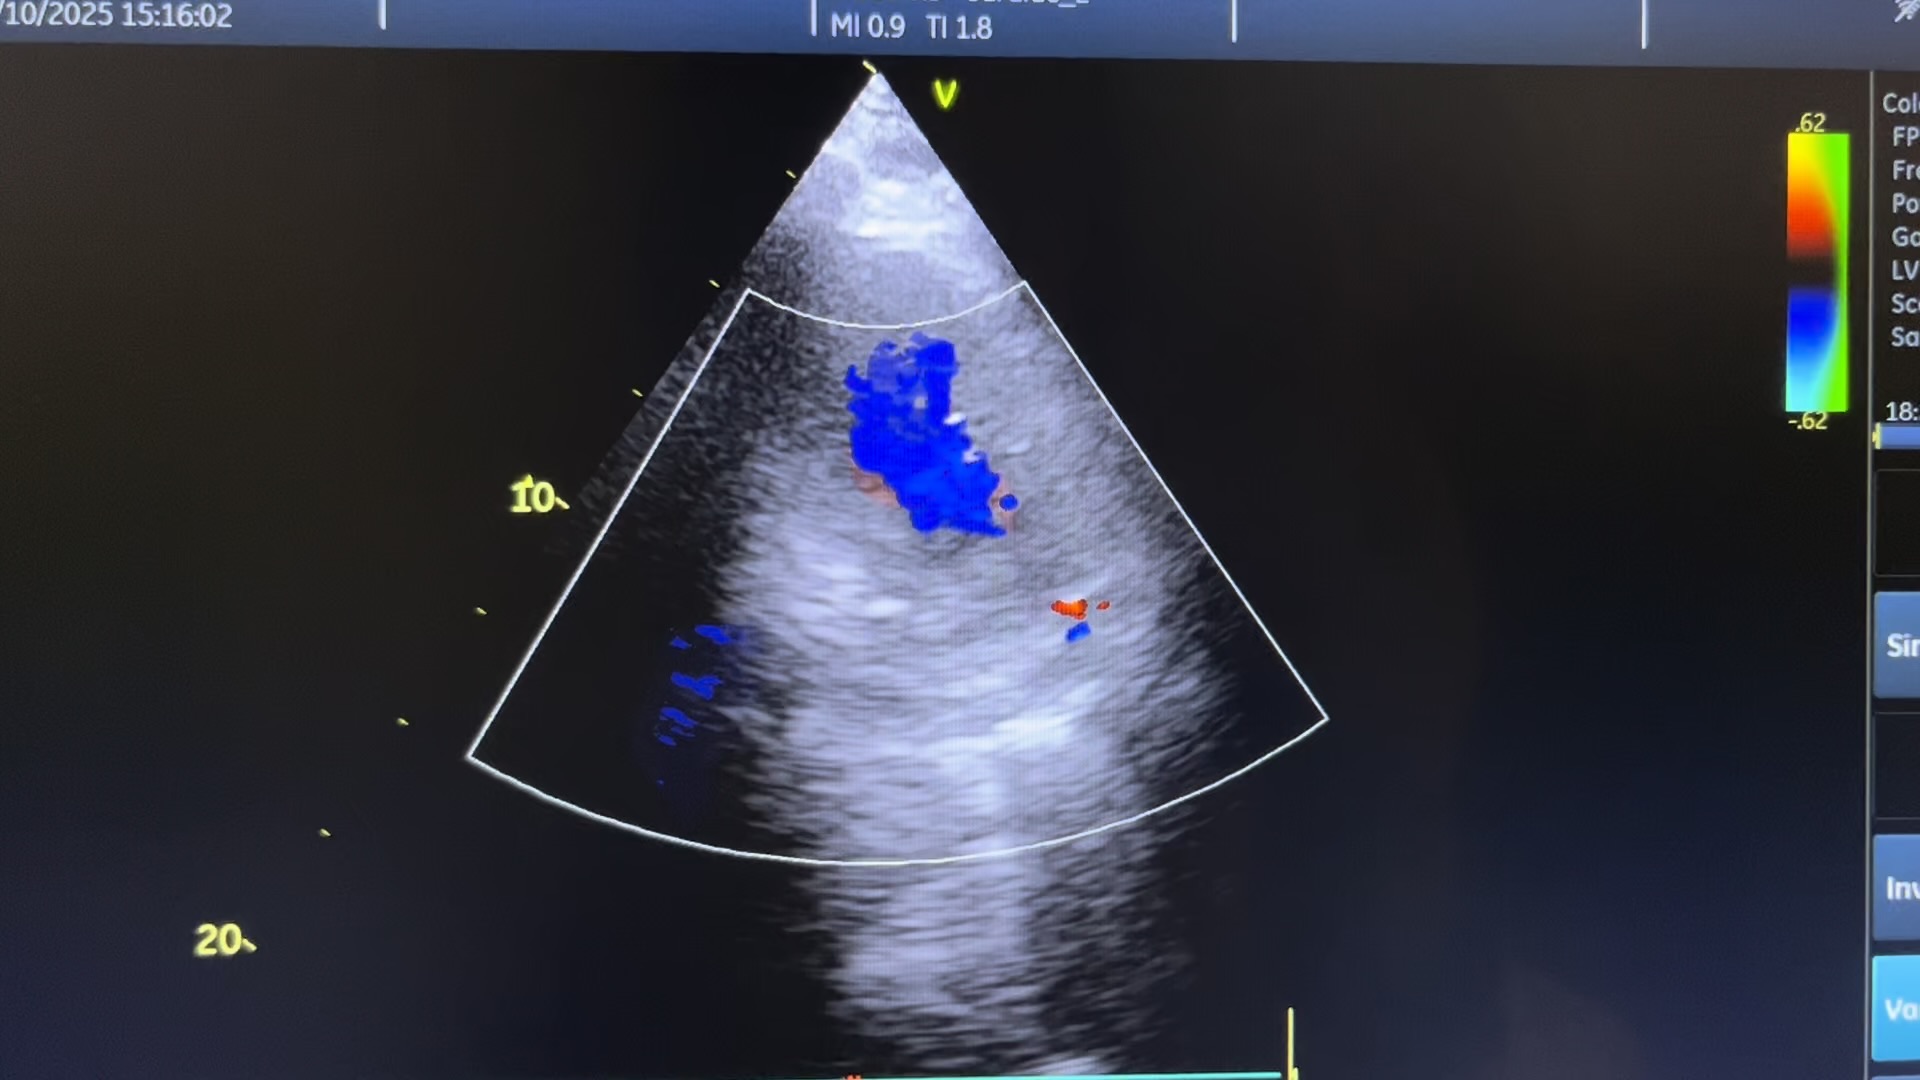

临床申请单上面无任何信息,看了床头牌才知道急性心梗入院,看左室长轴(可惜没拍图)心尖四腔心时都发现左房后外侧有一个囊性回声66✖️40mm左右,左房受压变得很小,一上彩,好家伙~穿孔了!询问值班医生,说心梗是广泛前壁,不符合啊,那多切面看吧,怎么看都是侧壁下后壁动的不行,侧壁基底段穿孔。

心尖四腔看到左室侧壁基底段异常血流

心尖四腔看到左室侧壁基底段穿孔处异常血流

很容易会把这个大血肿看成左房,前缘遮挡二尖瓣处,给人一种二尖瓣有问题的假象